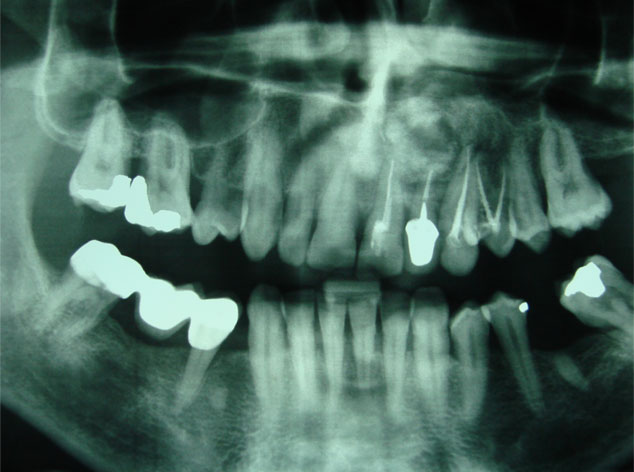

Aunque su estirpe anatomopatológica sea benigna, son quistes que en algunos pacientes provocan grandes destrucciones maxilares, porque crecen de forma asintomática durante años.

Su cirugía es sencilla y está basada en la extracción del quiste con criterios conservadores, y en la reconstrucción del defecto creado por la limpieza quirúrgica.

Para la reconstrucción, aconsejamos hacerlo en la misma intervención y con las bases de ingeniería tisular de la regeneración ósea guiada. Utilizamos como material óseo inductor el fosfato tricálcico tipo beta, mezclado con sangre del paciente y protegido con membrana de regeneración reabsorbible.